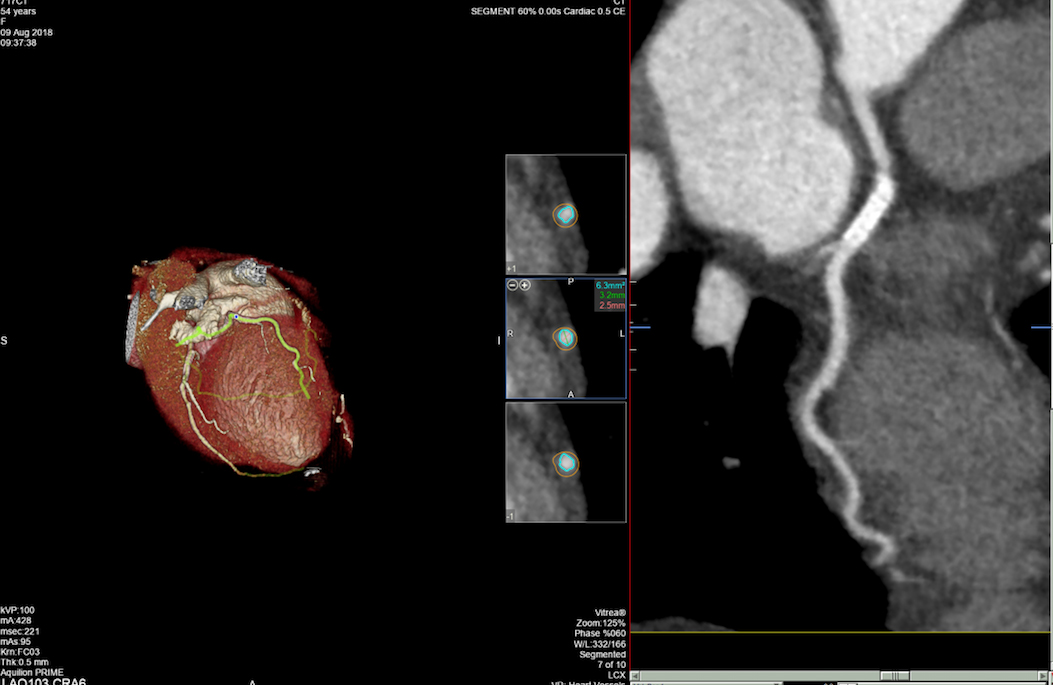

• MSCT koronarografija (prikaz krvnih žila srca CT-om, bez neugodnosti i komplikacija koje nosi klasična koronarografija), u saradnji s Poliklinkom dr.Al-Tawil